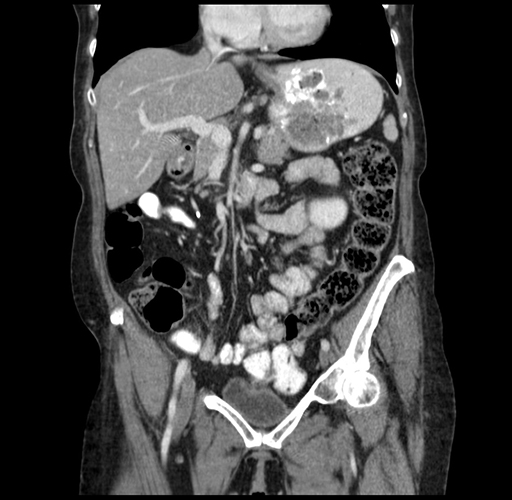

Pre-Chemo: Coronal Venous

Coronal Venous